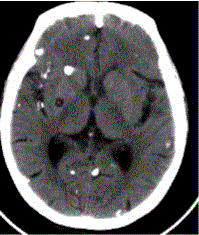

问题 患者男,45岁。头痛、癫痫10余年。查体:无发热,双侧肢体肌力正常。脑电图示双侧额颞叶棘波放电。CT表现如下图。 可能的诊断为

选项 A.包虫 B.囊虫 C.结核 D.转移瘤 E.真菌感染 F.甲状旁腺功能减低

答案 BC